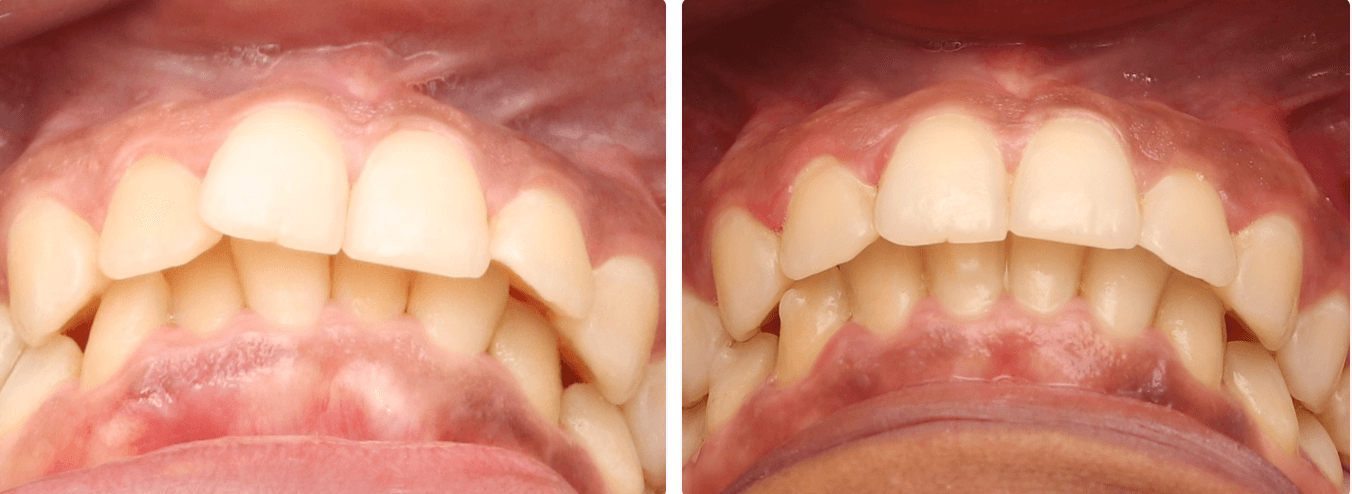

Mordida aberta anterior:

Quando é favoravel ao perfil do paciente, planejamos uma extrusão e retroinclinação dos dentes anteriores, junto de uma intrusão dos dentes posteriores, esse ultimo ocasiona em uma rotação da mandíbula para obtenção desse resultado.

Tratamentos que envolvem correção de mordida aberta são longos e geralmente é necessário uso de mecânicas elásticas e attachments, e geralmente nos dentes anteriores.

Movimentos de extrusão são de baixa previsibilidade com alinhadores, e em casos de perda de tracking podem ser utilizadas técnicas como “bootstrap”, para auxiliar na recuperação de tracking.

Mordida profunda:

Mordida profunda é um caso difícil mas possível de ser solucionado com alinhador, a solução desse tratamento pode ser relacionada com intrusão inferior ou superior, algo a ser determinado pela posição dos centrais superiores (Indicado na foto de repouso, confira nosso documento de Análise estética).

A intrusão tem uma previsibilidade baixa para a movimentação do alinhador, depende da instalação de muitos attachments para ancoragem e realização de uma movimentação estagiada para melhor resultado, dividindo movimentos entre caninos e incisivos por exemplo (Padrões de movimentação com os alinhadores)

O movimento de intrusão é bem comum de ter um resultado aquém do planejado virtualmente, considere refinamentos.